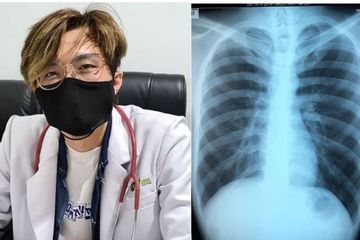

Akibat Merokok Paru Paru Dokter Tirta Serupa Orang 50 Tahun Kena Covid 19 Auto Mokad Semua Halaman Grid Health

Akibat Merokok Paru Paru Dokter Tirta Serupa Orang 50 Tahun Kena Covid 19 Auto Mokad Semua Halaman Grid Health

Akibat Merokok Paru Paru Dokter Tirta Serupa Orang 50 Tahun Kena Covid 19 Auto Mokad Semua Halaman Grid Health

Akibat Merokok Paru Paru Dokter Tirta Serupa Orang 50 Tahun Kena Covid 19 Auto Mokad Semua Halaman Grid Health